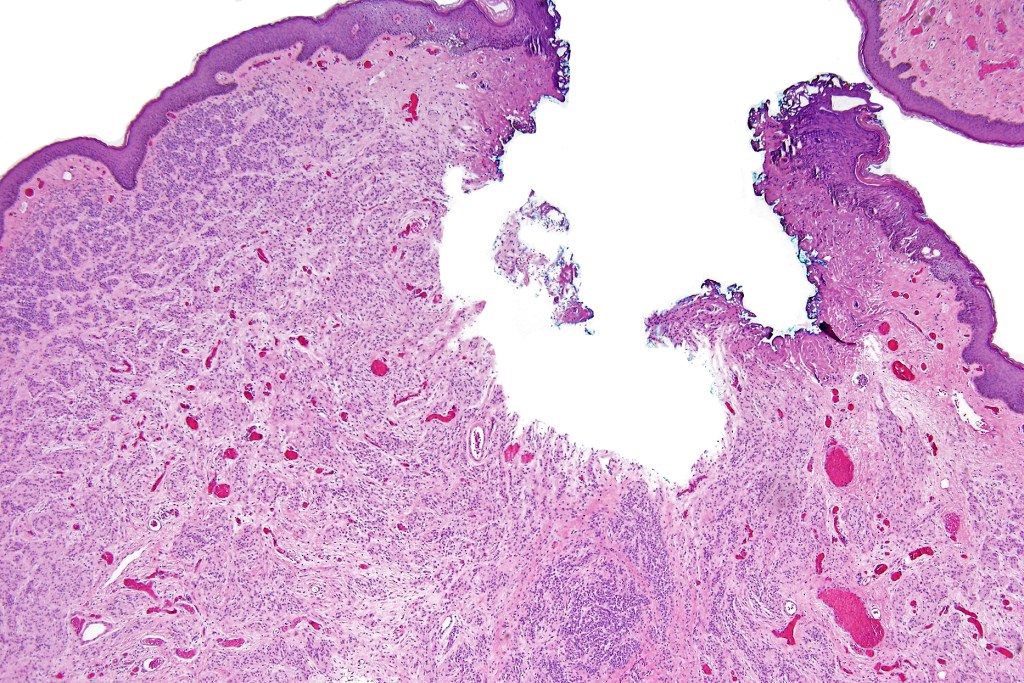

•Junctional/compound

•Large dyscohesive nests with retraction artifact, not restricted to the tips of the epidermal ridges

•Bridging common, often over multiple rete ridges

•Dermal fibrosis (sometimes lamellar)